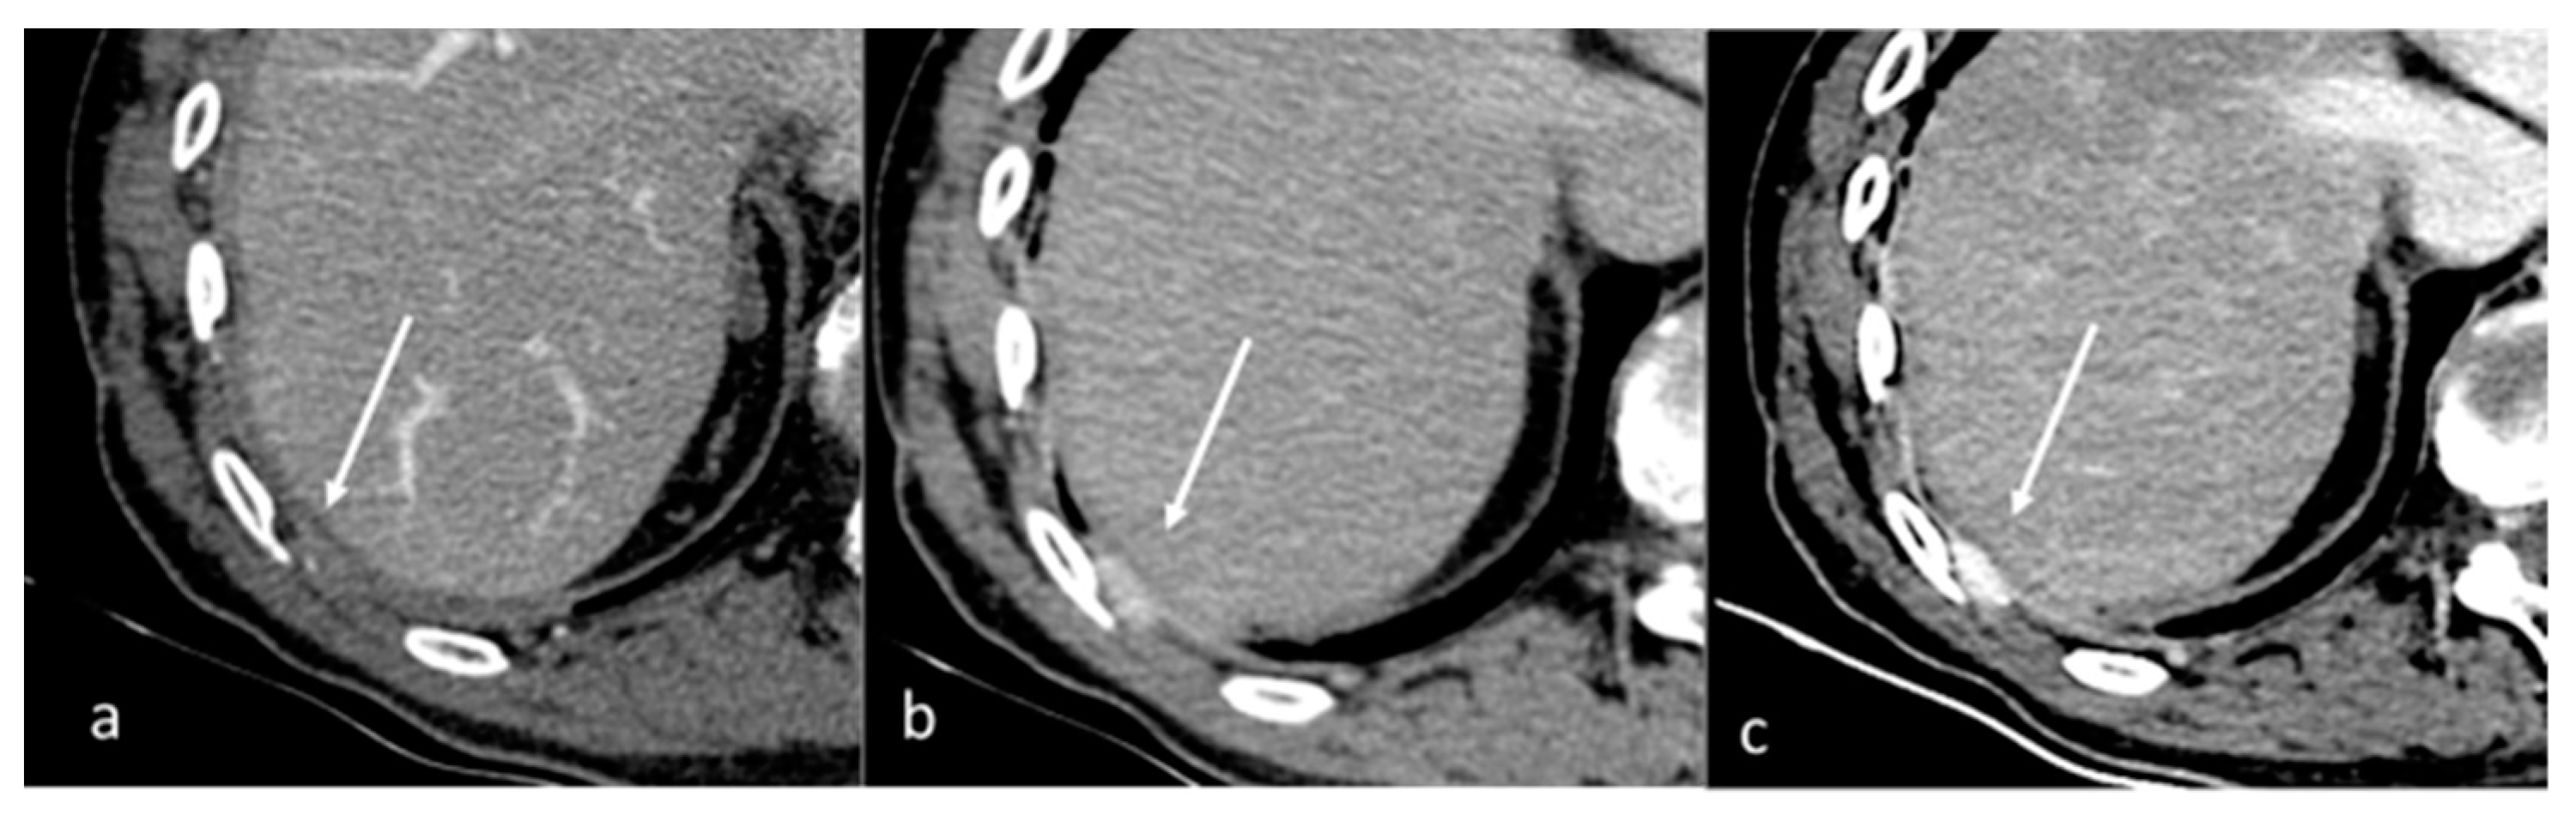

- Lennartz, S.; Le Blanc, M.; Zopfs, D.; Hokamp, N.G.; Abdullayev, N.; Laukamp, K.R.; Haneder, S.; Borggrefe, J.; Maintz, D.; Persigehl, T. Dual-Energy CT-derived Iodine Maps: Use in Assessing Pleural Carcinomatosis. Radiology 2019, 290, 796–804. [Google Scholar] [CrossRef]

- Zhang, X.; Duan, H.; Yu, Y.; Ma, C.; Ren, Z.; Lei, Y.; He, T.; Zhang, M. Differential diagnosis between benign and malignant pleural effusion with dual-energy spectral CT. PLoS ONE 2018, 13, e0193714. [Google Scholar] [CrossRef] [PubMed]